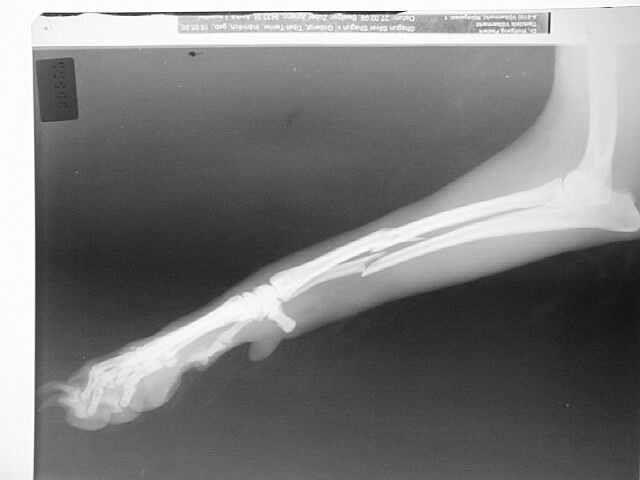

Oberarm-Trümmerfraktur

Marknagelung